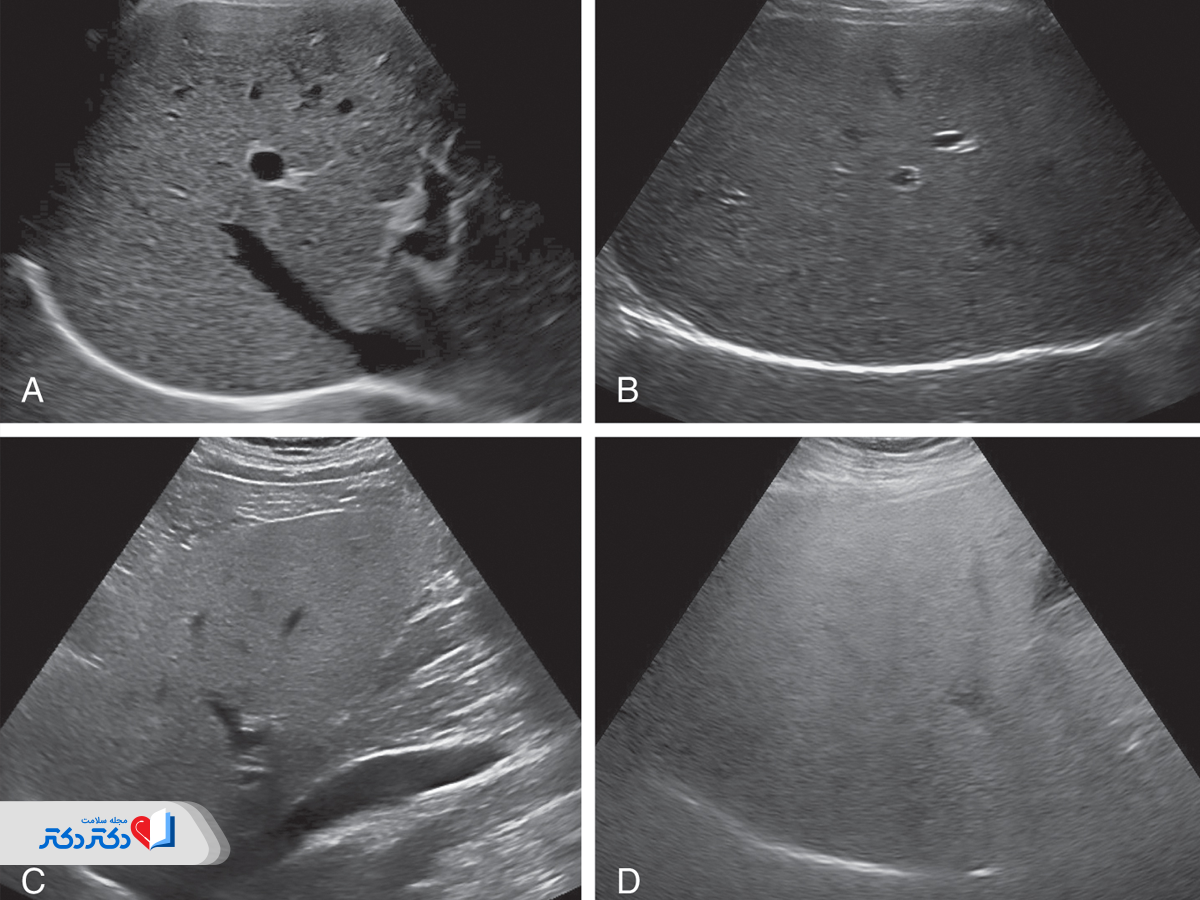

تشخیص کبد چرب با سونوگرافی از کبد

زمانی که علائم کبد چرب از روی چهره قابلمشاهده نیست، سونوگرافی کبد برای تشخیص کبد چرب انجام میشود. پزشک با مشاهده تصاویر سونوگرافی، تجمع چربی در بافت کبد را شناسایی میکند. در این تصاویر، وجود تجمع چربی معمولا با کاهش اکوژنیسیته کبد نمایان میشود. بهعبارت سادهتر، کبد چرب معمولا روی تصویر کمنورتر از بافتهای دیگر است.

با پیشرفت بیماری، احتمالا نشانههایی از التهاب و آسیب کبدی نیز در تصاویر به چشم میخورد. علاوهبر این، پزشک بهکمک نتایج سونوگرافی کبد چرب دگرگونیهای ساختاری کبد را بررسی و نواحی مشکوک به فیبروز کبدی یا دیگر مشکلات را شناسایی میکند.

در زیر، عکس سونوگرافی کبد چرب گرید را مشاهده میکنید.

درجهبندی کبد چرب در نتیجه سونوگرافی

درجهبندی کبد چرب در نتیجه سونوگرافی به ارزیابی میزان تجمع چربی در بافت کبد کمک میکند. این درجهبندی معمولاً به سه دسته تقسیم میشود:

- درجه ۱ (خفیف) که نشاندهنده تجمع چربی محدود است؛

- درجه ۲ (متوسط) که تجمع چربی بیشتر است و ممکن است با عوارضی همراه باشد.

- درجه ۳ (شدید) که نشاندهنده تودههای چربی وسیع در کبد است که میتواند به نارسایی کبد و سایر مشکلات جدی منجر شود.

این ارزیابی به پزشکان کمک میکند تا برنامههای درمانی مناسب را برای مدیریت و بهبود وضعیت کبد تعیین کنند.